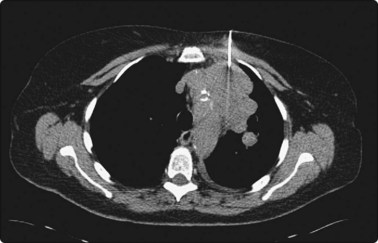

CT scanning

There are very few areas of the body which cannot be biopsied under CT control, and extremely small lesions can be sampled. Focal masses of several millimeters within the lung and skull base (Fig. 3.2) can be biopsied and retroperitoneal biopsies are limited only by availability of needles long enough to traverse the abdomen of large patients. Traversing with fine needles offers fewer risks compared with the larger-caliber needles.7 CT gantry tilt also further facilitates lesion access where appropriate.

Localization of the needle tip within a lesion is very accurate with CT (Fig. 3.3). It provides detailed cross-sectional images of the body which are not limited by the same physical properties as are ultrasound images, such as interference from bowel gas and bone.

image

Fig. 3.3 Inflammatory lesion of the lung

Tissue is obtained for culture and other appropriate tests. Local anaesthetic is visible in the subcutaneous tissues.